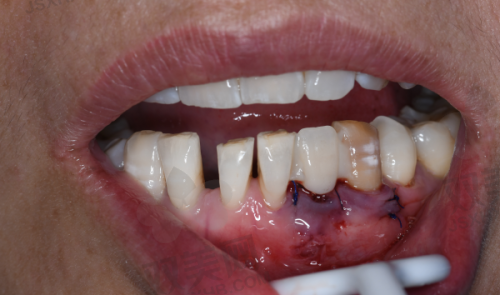

2. **种植牙**:种植牙是北京博康泰口腔医院的特色项目之一。医院引进了精良的种植牙技术和设备,医生具备丰富的种植牙经验,能够为患者提供安心、效率高的种植牙服务。种植牙可以有效解决牙齿缺失问题,修复牙齿的咀嚼功能,并且外观自然,使用寿命长。

3. **微创技术**:医院注重采用微创技术进行治疗,减少患者的痛苦和创伤。在拔牙、种植牙等手术中,医生会尽量减少对周围组织的损伤,缩短患者的修复时间。例如,在种植牙手术中,采用微创种植技术,切口小、出血少,术后疼痛轻,患者能够更快地修复正常生活。